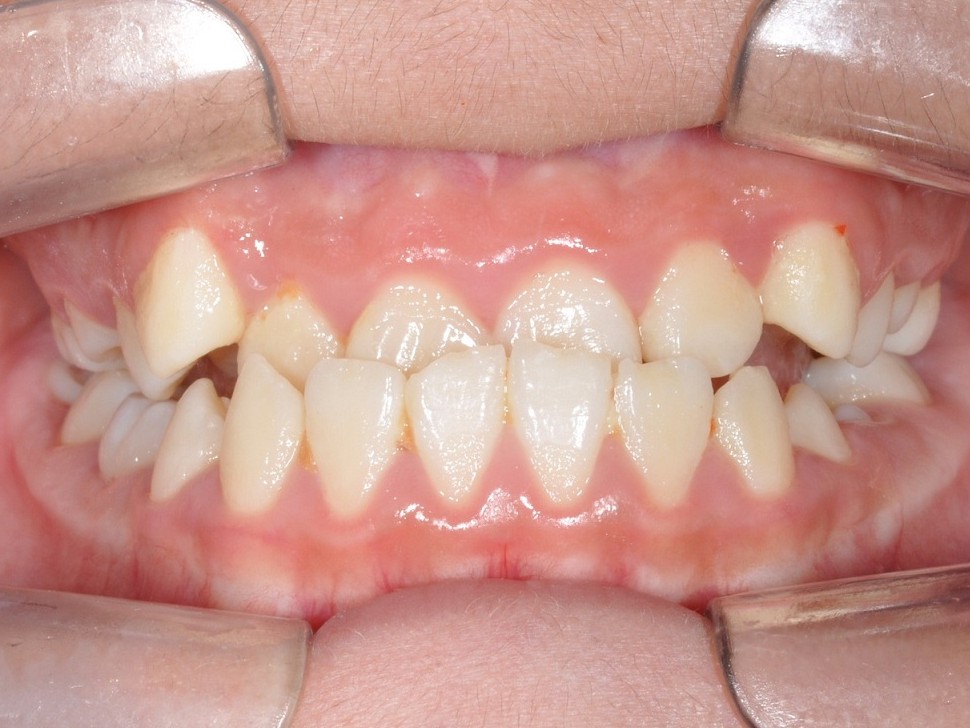

치료 전 : 반대교합+경도 골격적 비정상

치료 후 : 교정으로 반대교합 해소